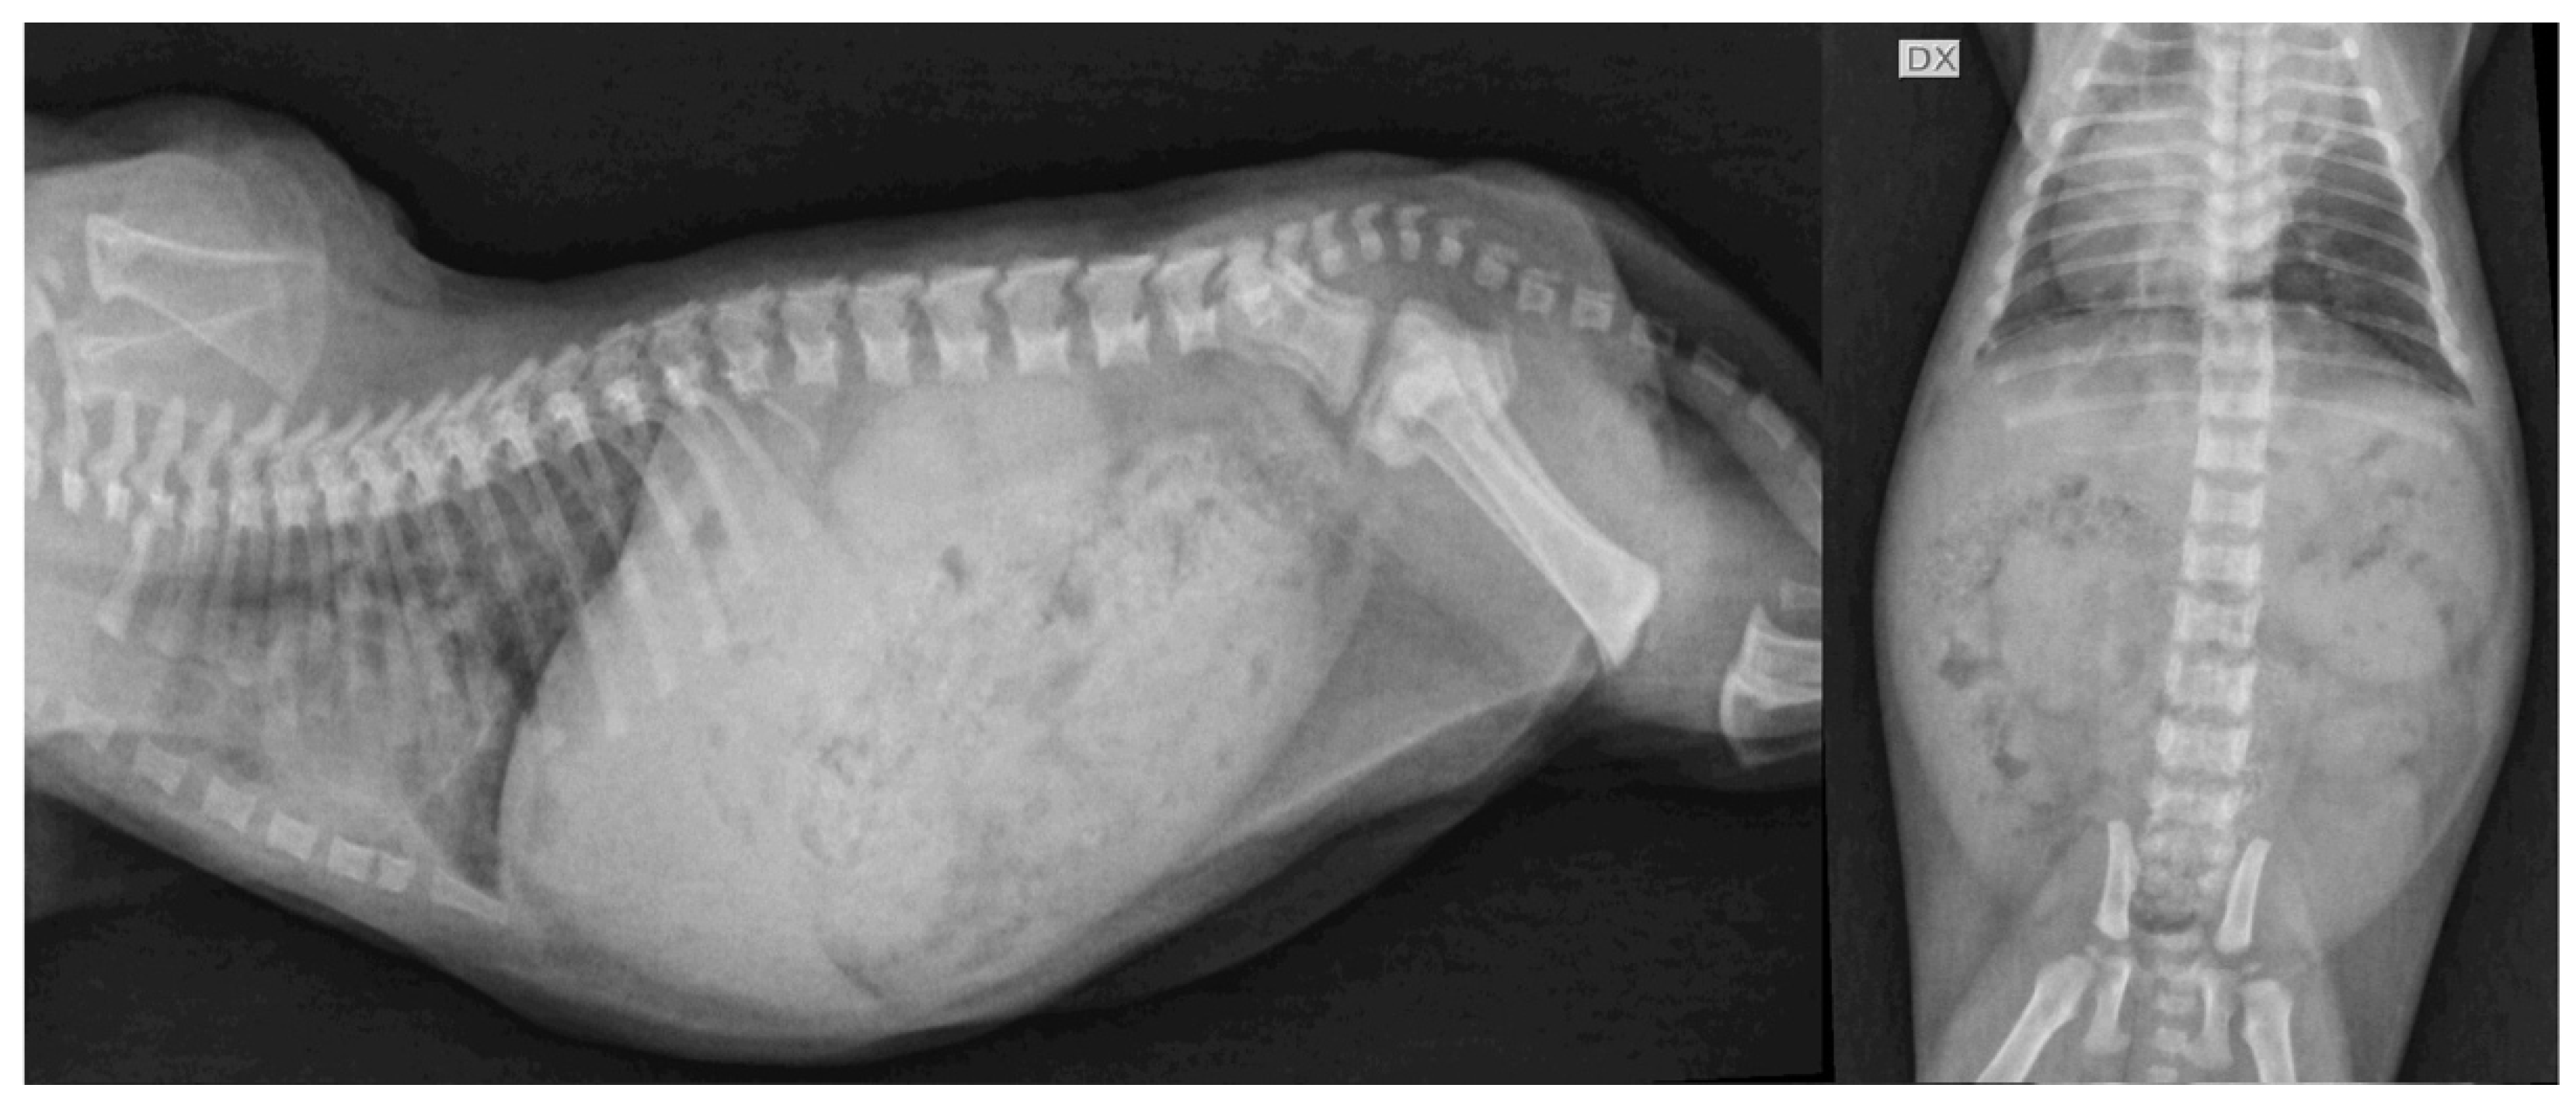

4.1. Case Description